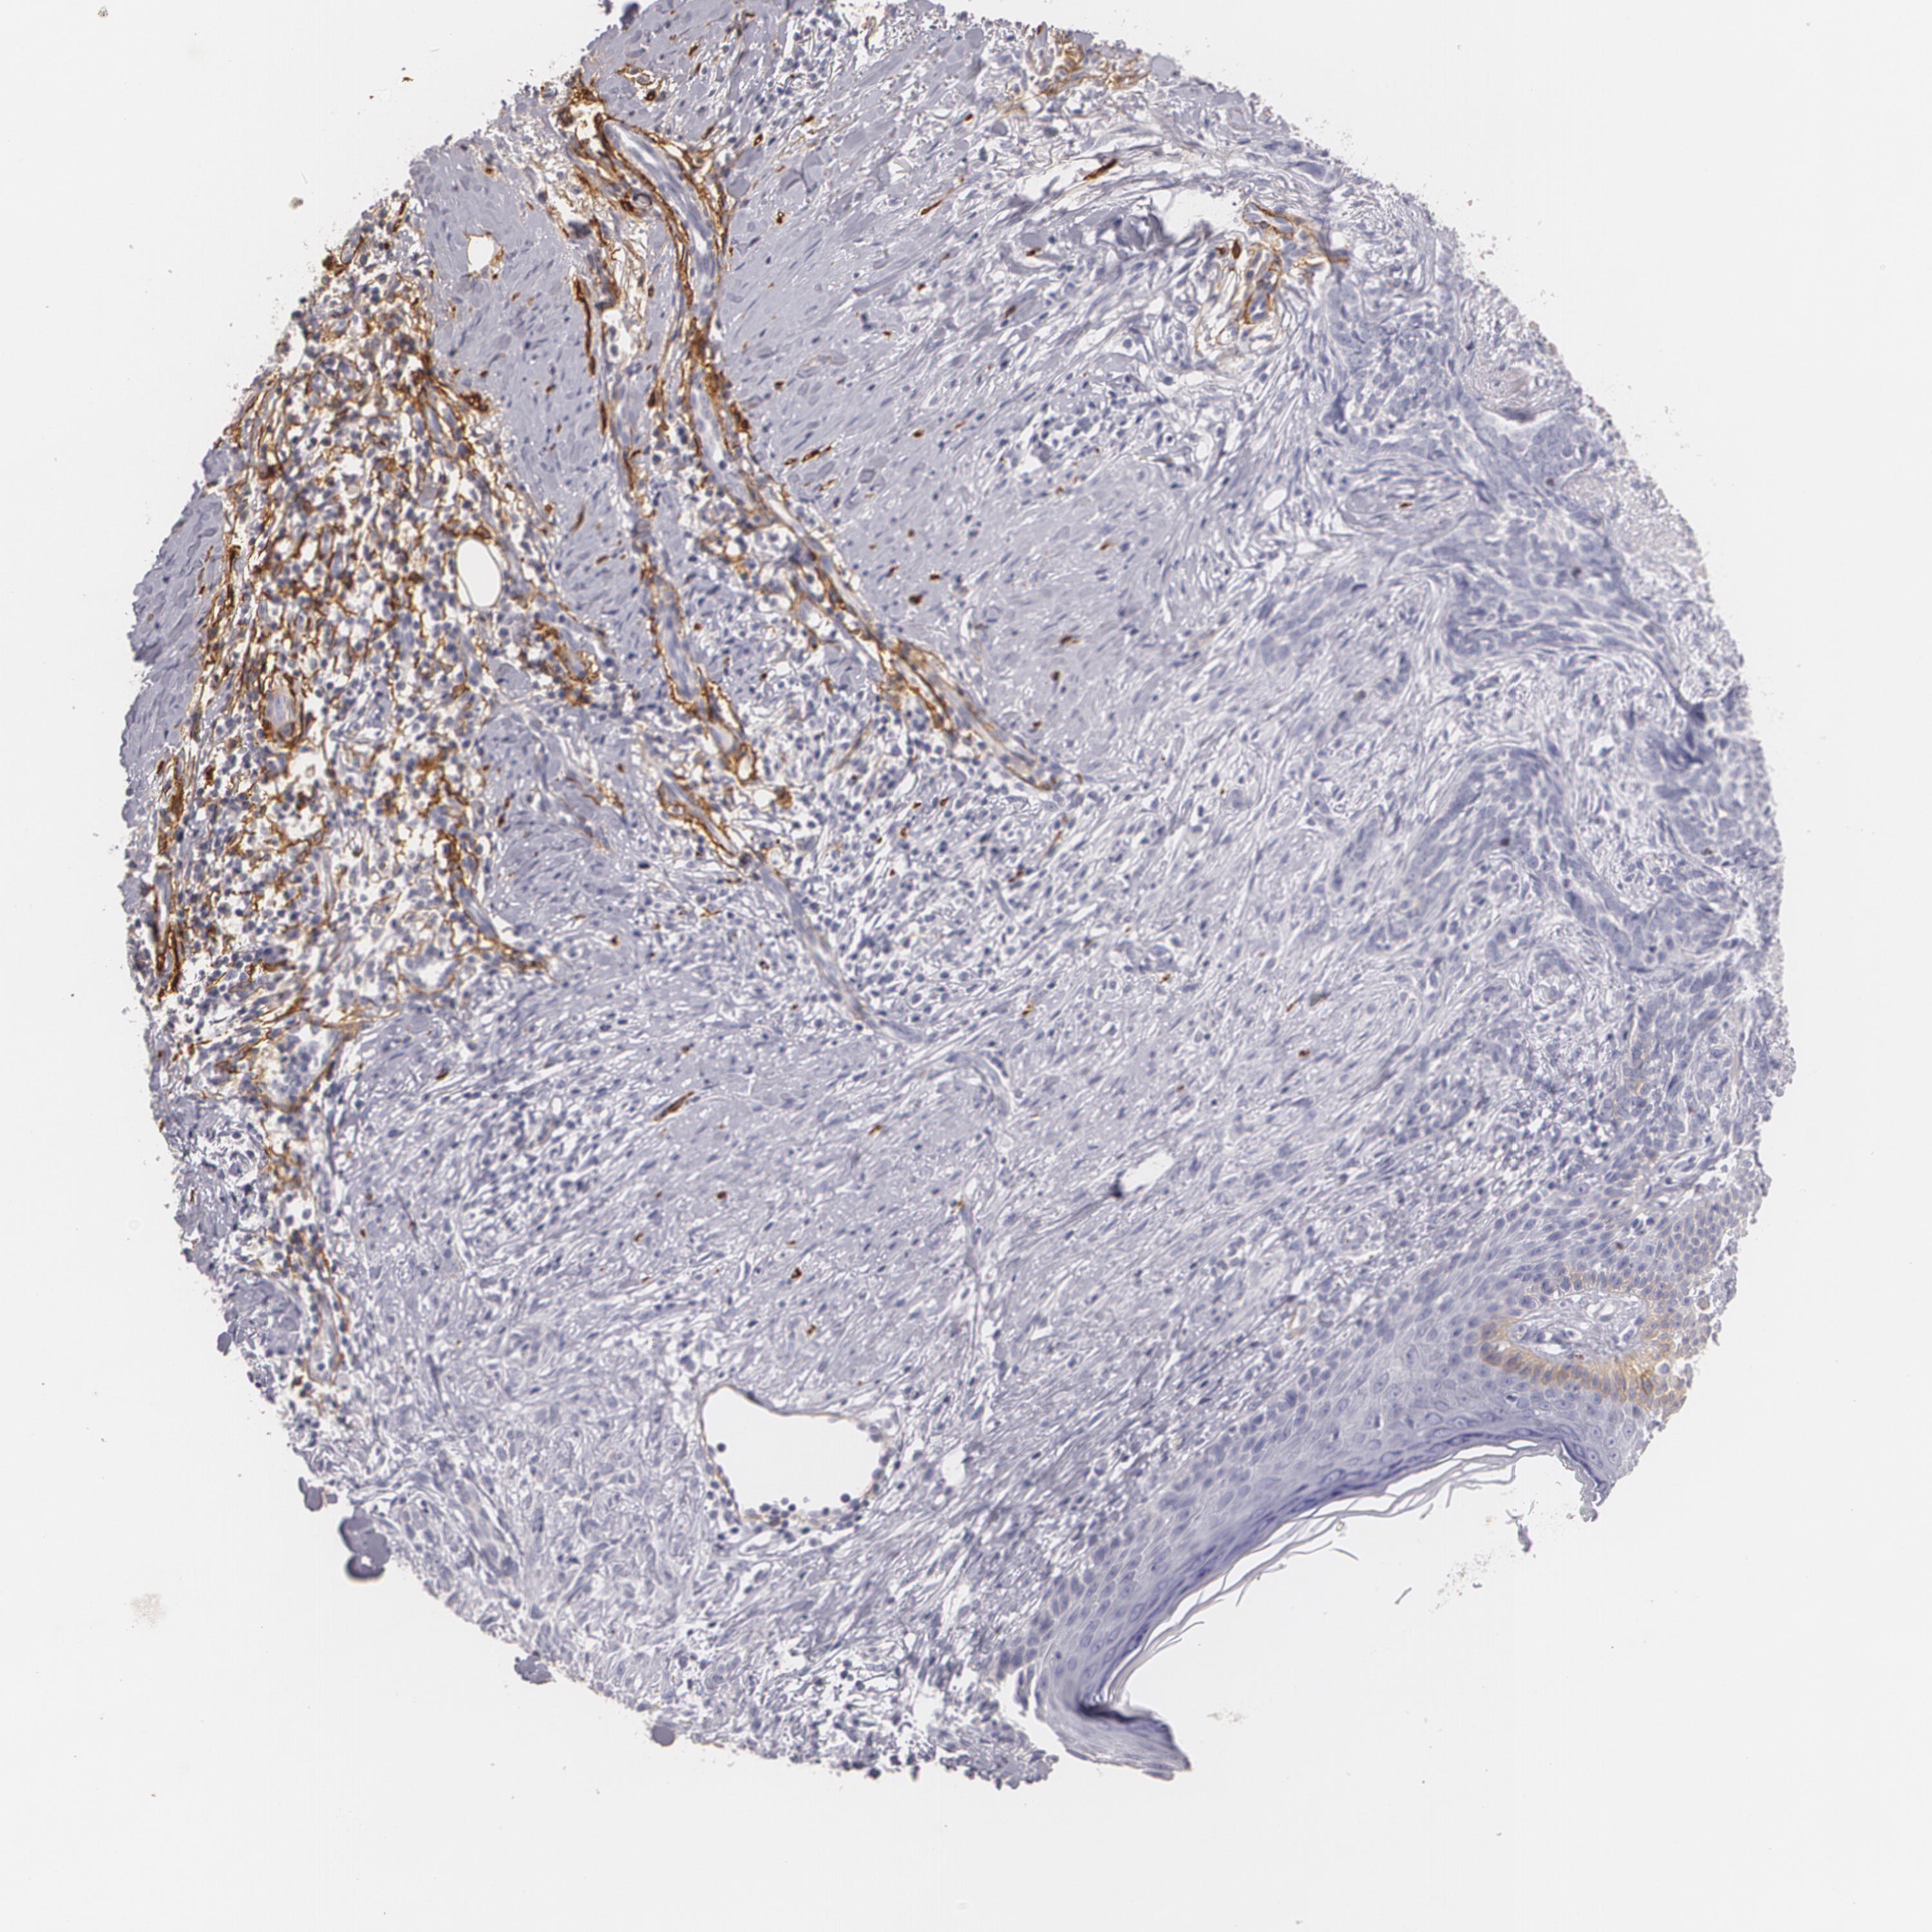

SKIN CANCER - Protein expressioni

A mouse-over function shows sample information and annotation data. Click on an image to view it in a full screen mode. Samples can be filtered based on level of antibody staining by selecting one or several of the following categories: high, medium, low and not detected. The assay and annotation is described here.

Antibody staining in the annotated cell types in the current human tissue is reported as not detected, low, medium, or high, based on conventional immunohistochemistry profiling in selected tissues. This score is based on the combination of the staining intensity and fraction of stained cells.

Each image is clickable and will lead to virtual microscopy that enables deeper exploration of all samples and also displays staining intensity scores, fraction scores and subcellular localization as well as patient and tissue information for each sample.

Antibody HPA004765

Antibody CAB000143

Antibody CAB001995

Squamous cell carcinoma, NOS

Basal cell carcinoma